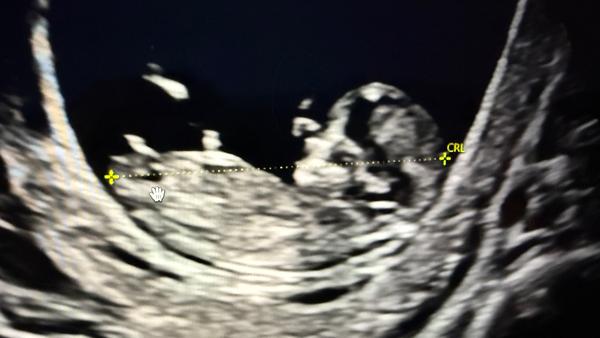

Může někdo určit pohlaví podle ultrazvuku ve 13+3 týdnu?

@hollynka těžko říct, jestli to co je vidět je pohlavní hrbolek, tak je to holčička. Já si podle něj sama určila tenkrát dceru 😁teď jsem to věděla z NIPT. Jsou lékaři, co se trefí už ve 13 tt, co to umí. A pak jsou i lékaři, kteří i kolem 20 tt vahaji.

Mě přijde, ze holka.

@ovesova taky bych řekla, ze holka... vypadá to stejně jako z naseho UZ ve 14tt 😃

@hollynka myslim si, ze holka 🤗